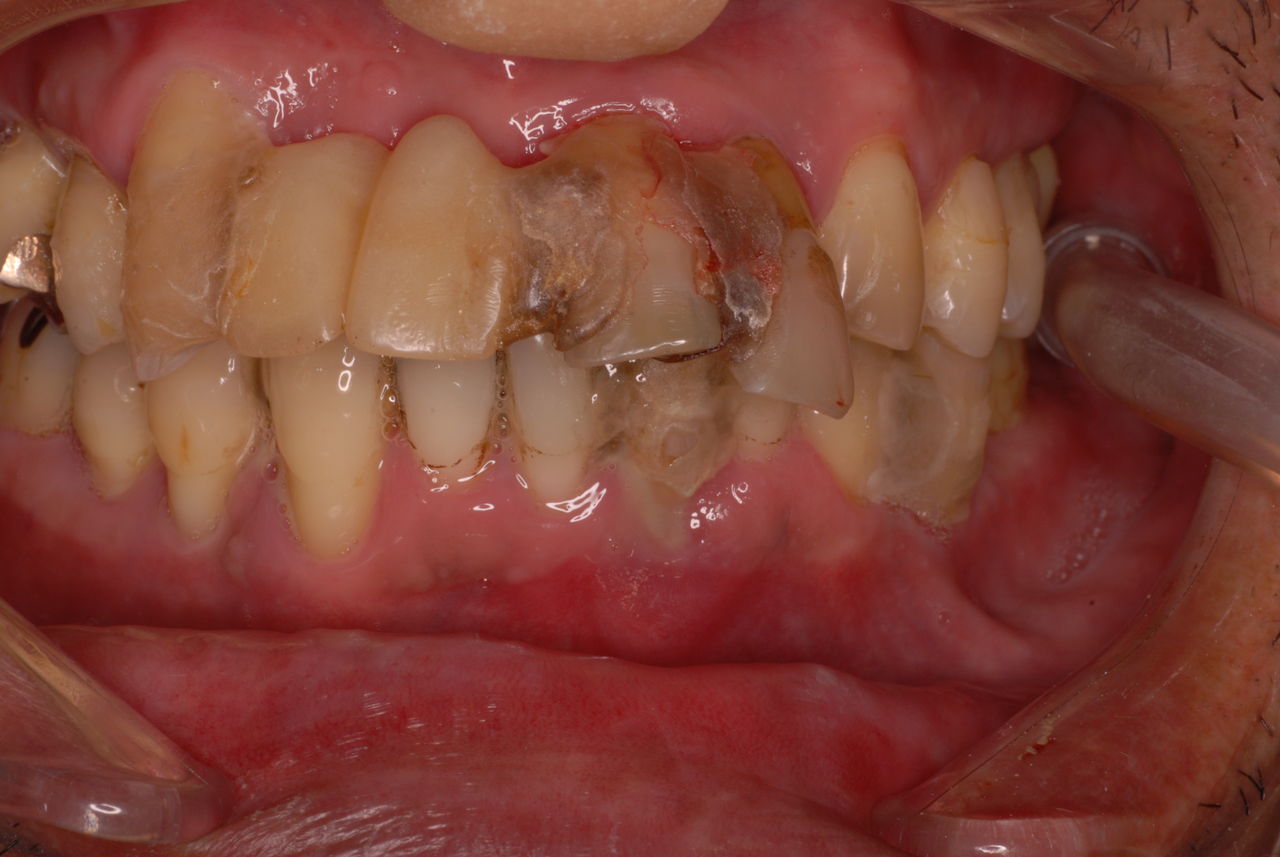

70代の患者ですが上の歯は残根一つ全て歯は無し。

下顎、殆ど歯はなく歯周病で抜けそうな歯と虫歯だらけの歯、適合の悪い銀歯が入っていてそれも虫歯と歯周病で危ない状態でした。入れ歯は下の入れ歯は入れたことがないようです。(ため息)痛くて入れたことがないそうです。

左下の歯は歯の中の治療も?ですごい歯周病を患い歯茎の穴(ポケットと呼ばれるところ)から膿が出ているのです。ばい菌と毒素で骨が溶けて深い穴ができてそこにまたバイキンと毒素がたまるという悪循環ができているのですね。

右下の歯は歯の中の治療もあやしいのですが、金属と歯の間がすでに虫歯で崩壊し始めています。

プラークというバイキンと毒素と食べかすの塊が歯の周りや歯茎にまとわりついて虫歯になり且つ重症の歯周病を患っています。